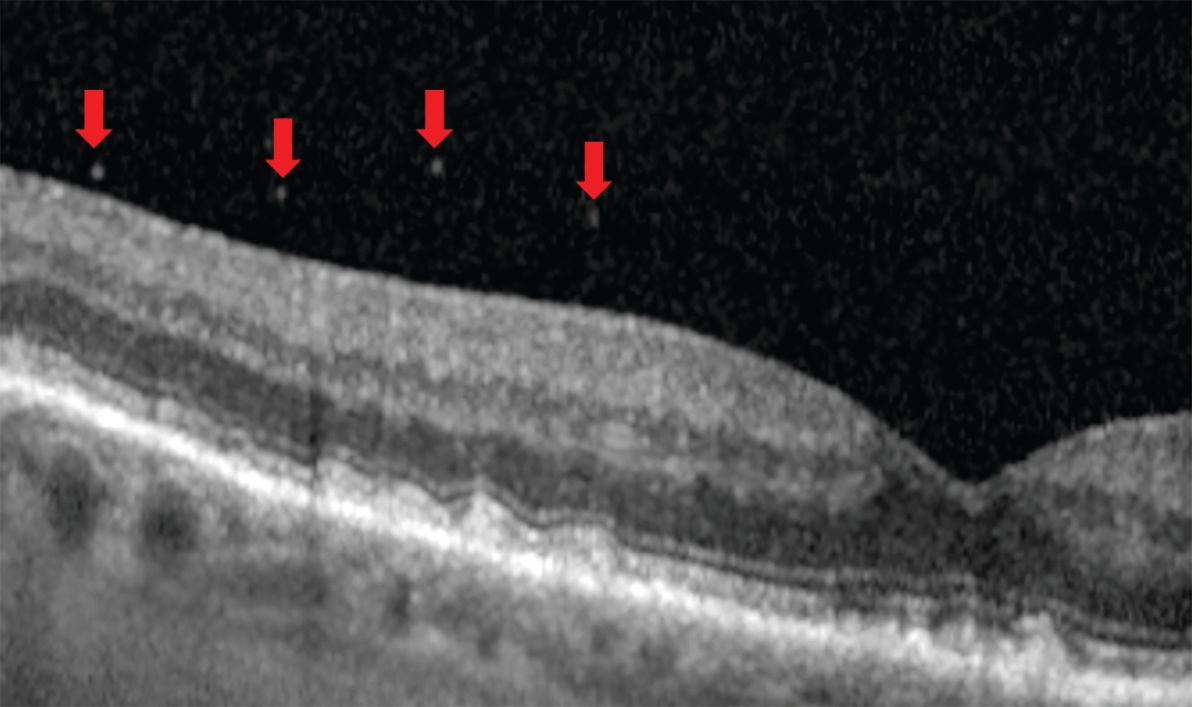

Figure 4. Anteriorly focused widefield Spectralis optical coherence tomography of 2 patients. a) Posterior precortical vitreous pocket (PPVP). b) A prominent supramacular bursa (inset) versus a more subtle one (arrow). c) Only about half of eyes have a collecting channel. d) Septum e) Martegini area f) Cloquet’s canal. Image courtesy of Jim Williamson, OD, FAAO, FORS.

Detailing the structure, however, required other methods. Early work included scanning electron microscopy and then fluorescein staining of postmortem eyes.9 Time-domain OCT (TD-OCT) added an in vivo vitreous view unlike anything previously seen. Today, higher-resolution spectral-domain OCT (SD-OCT) and swept-source OCT (SS-OCT) allow the detection of more specific features (Figure 4). Further, the employment of OCT in the retinal periphery debunked the previously held belief of a “vitreoretinal interface change” as the cause for dark or white without pressure and proved the source to be an attenuated or hyperreflective ellipsoid zone (Figure 5).13

One of the most interesting vitreous findings of early investigators is the posterior precortical vitreous pocket (PPVP), also sometimes referred to as the premacular bursa or just bursa, which means sac or pouch (Figure 4). Located above the macular area, this dome- or boat-shaped liquified space measures on average about 0.7 mm high and 6.4 mm wide.14 Its posterior border contains a thin layer of vitreous cortex while the vitreous gel outlines the anterior border.9 Therefore, the PPVP spares the premacular vitreous cortex from anterior gel contraction, which plays a key role during vitreous degeneration.14 It also explains the “wolf’s jaw” appearance of fibrovascular proliferation in proliferative diabetic retinopathy. The superior and inferior temporal locations along the arcades coincide with the wall of the PPVP (Figure 6). If bleeding into the PPVP occurs, the hemorrhage will take on a boat-shaped appearance as it collects at the wall’s bottom due to gravity.